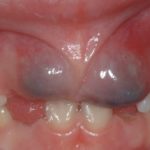

Также если родители не могут понять, почему синеют десна у детей, стоит отправиться к стоматологу. Чаще всего причины заключается в поражении мягких тканей инфекцией, которая скапливается в ранке и вызывает воспаление. Нередко младенцы тоже сталкиваются с подобной проблемой при прорезывании зубов. Синяя десна у ребенка наблюдается при травмировании тканей резцом на этапе его активного роста. Возникает подкожная гематома – сегодня эту проблему успешно лечат в любой клинике.